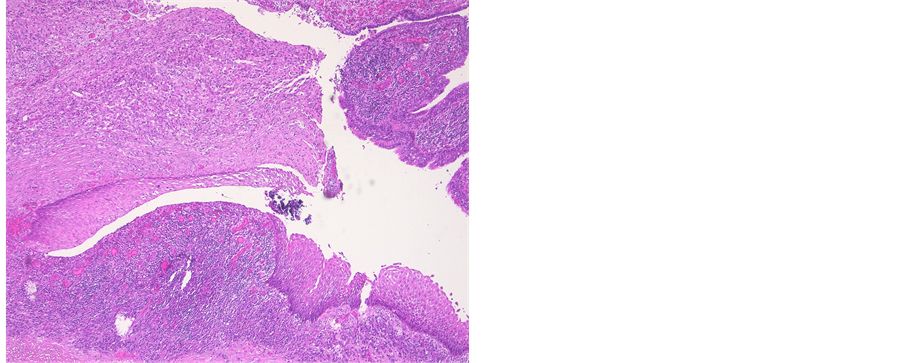

Histological diagnosis included four tailgut cysts, two epidermoid cysts and one chordoma. An overview is summarized in Table 3. Maximal diameter ranged from 2.8 cm to 10 cm. Mean diameter was 5.3 cm. Excision was microscopically complete in all cases. Tailgut cysts were characterized by their multicystic aspect, thin wall, mucoid material, various epithelial types and a surrounding disorganized muscle layer (Figure 4). Epidermoid cysts were lined with malpighian epithelium, containing laminated keratin contents. An inflammatory response, based on rupture, was present in one cyst (Figure 5). No atypia, sacral bone defects or calcifications were noted. The chordoma consisted of multiple lobules and physaliphorous cells with intracytoplasmic vacuoles (Figure 6). There were no regions of chondroid differentiation or chondrosarcoma. The cells labeled with cytokeratin and S-100 protein. The proliferation marker Ki67 was positive in less than 2% of all cells. Sacral destruction was noted.

Histological conformation is made postoperative and determines further follow-up. Epidermoid cysts are unilocular lesions, which are lined with stratified squamous epithelium and filled with clear fluid. They do not contain skin appendages, in contrast to dermoid cysts [8] [34] . Tailgut cysts are multicystic lesions, filled with mucoid contents and lined with ciliated columnar cells, squamous cells and transitional cells [20] [34] . Rectal duplication cysts are differentiated based on following criteria: an organized smooth-muscle coat (desmine staining), continuity with the rectum and a mucosal lining similar to the rectal mucosa [34] . Teratomas are diagnosed based on their three germ layers [9] [34] . The microscopic hallmark of chordomas are the physaliphorous cells, which contain glycogen or mucin. Conventional chordomas are characterized by the absence of mesenchymal components, in contrast to chondroidchordomas and chondrosarcomas. S-100 protein expression is typically present in both chordomas and chondrosacromas, while the latter does not express cytokeratin [39] .